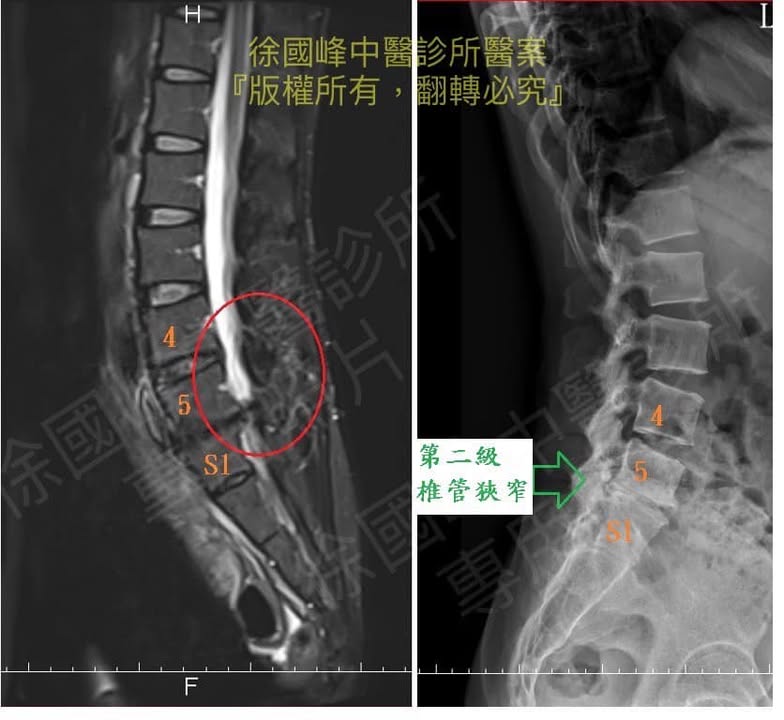

🔄經友人介紹來診所求醫,徐醫師從核磁共振完整評估以及結合動作醫學動態分析患部之病灶點,做了以下四個診斷。

1.腰椎核心肌群萎縮

2.L4L5;L5S1第二級椎孔狹窄

3.左側髖關節張力異常

4.梨狀肌症候群

👨⚕️評估:還沒出現馬尾症候群症狀,沒有大小便失禁,患者墊腳尖的力量還算穩定,肌肉也並無萎縮的症狀,基本上沒有嚴重到要開刀的程度。

影像學檢查:醫師大多會先進行身體檢查,找出患者不適處,並安排影像學檢查像是X光、肌電圖、斷層掃描(CT)、核磁共振(MRI)來確認主因,核磁共振的效果最佳,能夠直接看出椎間盤突出的位置和嚴重程度。